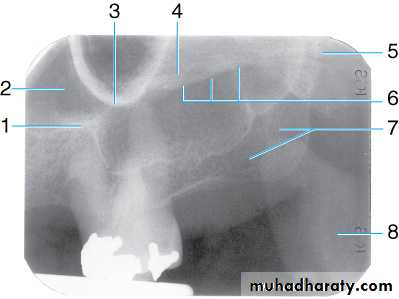

Radiograph of maxillary molar area. This radiograph shows (1) border (floor) of maxillary sinus, (2) maxillary sinus, (3) zygomatic process of maxilla, (4) zygoma, (5) lateral pterygoid plate, (6) lower border of zygomatic arch, (7) maxillary tuberosity, and (8) coronoid process of the mandible

Radiograph of maxillary molar area. This radiograph shows (1) hamulus (hamular process), which is a downward projection of the medial pterygoid plate, (2) lateral pterygoid plate, (3) coronoid process of the mandible, (4) maxillary tuberosity, and (5) maxillary sinus

Radiographic Anatomy Basics

Coronoid process of the mandible may be imaged on intraoral radiographs of the maxillary posterior region. Note the position of the film holder when exposing a maxillary posterior periapical radiograph. The coronoid process of the mandible will most likely be imaged on this radiograph.